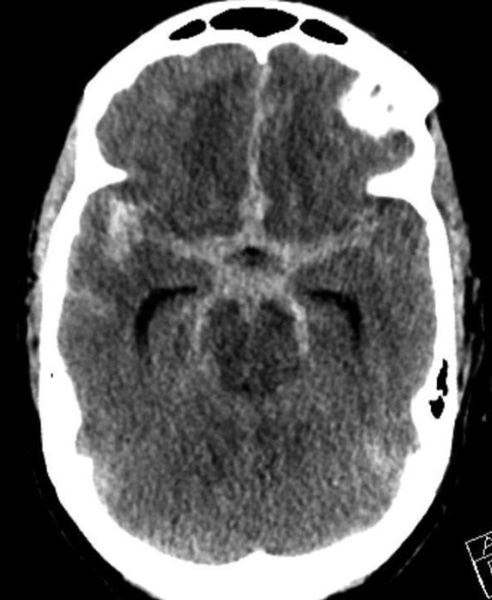

On admission, she presented as a GCS 3, was intubated, and stabilized hemodynamically in preparation for emergent catheter cerebral angiography, which revealed 2 discrete geographically located aneurysms – 1) Anterior Communicating and 2) Right ICA Supra-Clinoid Segment. (Figure 2.)

The Pattern of Hemorrhage was diffuse and generalized. On more careful analysis, however, there appeared to be focal hemorrhagic clot within the anterior inter-hemispheric fissure which raised greater suspicion for the Anterior Communicating Aneurysm as the source of hemorrhage. Although Acom Aneurysm was smaller, it’s irregular shape and eccentric “nipple” suggested potential rupture point. (Figure 3.)